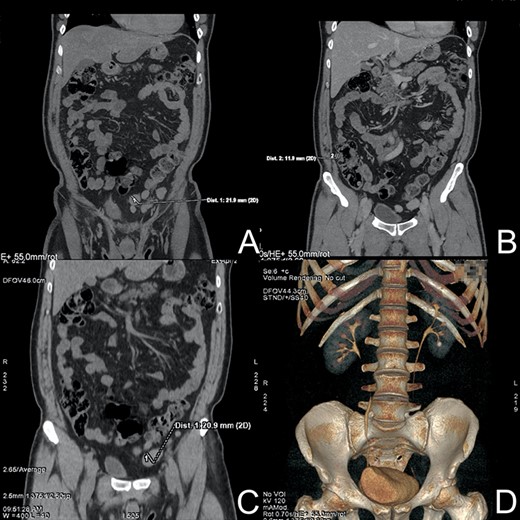

After proper preparation, CT-urography was performed. An imaging examination showed a 9 mm stone in the lower calyx of the left kidney. Attention was drawn to numerous pathological lymph nodes up to 3 cm in size, located along the left and right iliac axis, as well as in pelvic peritoneal fat, along the intestinal loops, especially the sigmoid colon and caecum (Fig. 1).

CT-urography. (A) Enlarged lymph node near sigmoid colon. (B) Pathological lymph node near the ascending colon. (C) Low-dose CT without contrast—lymph node. (D) 9 mm stone in the lower calyx of the left kidney.